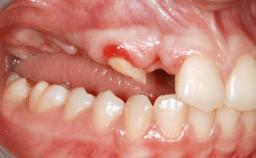

A 47-year-old Caucasian woman with a single-tooth edentulous space at the site of the left maxillary canine was referred for treatment. She had undergone traumatic extraction of this impacted canine several months before referral. Her chief complaint was the dissatisfying appearance of her smile. The patient desired a stable and esthetic rehabilitation of the site. Her dental history showed no evidence of periodontal disease or bruxism. She had no systemic diseases, was not taking any medications, and did not smoke. The extraoral examination revealed a high lip line and an inadequate soft-tissue volume at the defective canine site. Large black triangles were visible between the canine and its adjacent teeth.

| Soft Tissue Anatomy | Intact | Defective | |

| Bone Volume | Horizontally and vertically sufficient | Horizontally deficient | Deficient vertically or deficient vertically AND horizontally |